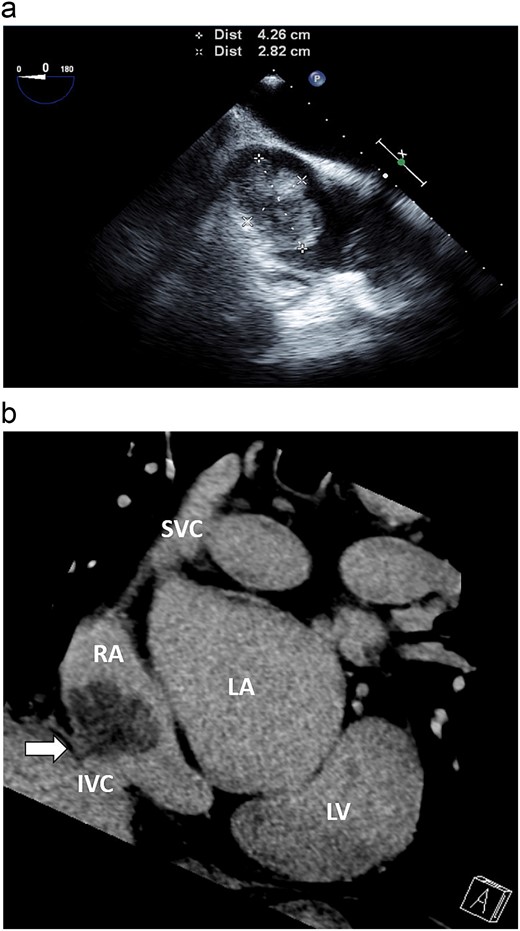

A 72-year-old male was consulted to our section for the management of a cardiac mass approximately 40 mm in diameter in the right atrium. On admission, he was in stable condition and had no symptoms. His chest X-ray showed a clear lung field and normal cardiothoracic ratio. His laboratory data were within normal limits. His transesophageal echocardiography demonstrated a mass of 42 × 28 mm in size, located in the inferior cavity of the right atrium. The mass was multiple lobulated, pedunculated, and had high mobility (Fig. 1a). In addition, its stalk was attached to the endocardium of the IVC orifice in a narrow range, as was similar to his preoperative coronary computed tomography (CT) scan (Fig. 1b). There were no signs of pulmonary thromboembolization. The mass had no relation to the tricuspid valve. Thus, we decided to surgically remove the tumor to prevent pulmonary embolization. The operation was performed via median sternotomy, followed by harvesting the autologous pericardium. Then, two venous cannulas in size of 28 Fr were inserted: the one was in the superior vena cava directly, and the other one was in the main pulmonary artery, respectively. We avoided usual IVC cannulation through the right atrium, which could have a considerable risk of fragmentation of the tumor during manipulation. Cardiopulmonary bypass was then started, and the core temperature was reduced to 20°C. Circulatory arrest was induced after cardioplegic heart arrest. Through a lateral right-atriotomy, there existed a lobulated, gelatinous, and smooth surfaced tumor in size of 43 × 38 × 25 mm in the inferior cavity of the right atrium (Fig. 2a). The tumor was completely resected successfully, including its stalk and the small lesion of the endocardiu of the IVC orifice. The deficit of the endocardium was closed with autologous pericardium (Fig. 2b). The circulatory arrest time was 19 min. The postoperative course was uneventful. Histopathological examination revealed the tumor, including the endocardium attached to its base, was completely resected (Fig. 3), and diagnosed it as a myxoma. A transthoracic echocardiography 3 years after surgery showed no signs of recurrence.

(a) Transesophageal echocardiography demonstrated that the mass was 42 × 28 mm in size, located in the inferior cavity of the right atrium, and was multi-lobulated, pedunculated, and highly mobile. (b) Coronary CT revealed a stalk on the endocardium of the IVC orifice (white arrow).